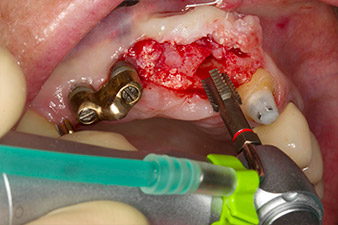

le forage pilote est effectué avec le nouvel Implantmed et le contre-angle WS-56 L

Fig. 2 : Deux mois plus tard, le forage pilote est effectué avec le nouvel Implantmed et le contre-angle WS-56 L (programme P1, ratio 1:1). Le refroidissement est effectué au moyen de la buse de pulvérisation située à gauche (pour les utilisateurs droitiers).